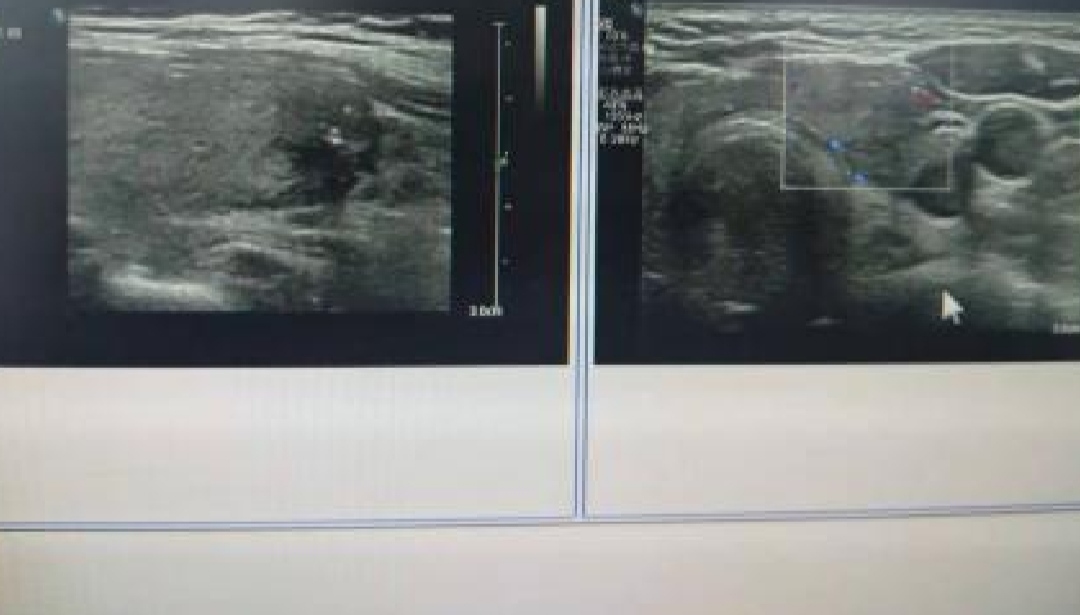

我立刻为他安排了甲状腺彩超,结果提示患者甲状腺弥漫性肿大,甲状腺多发囊实性结节3类。